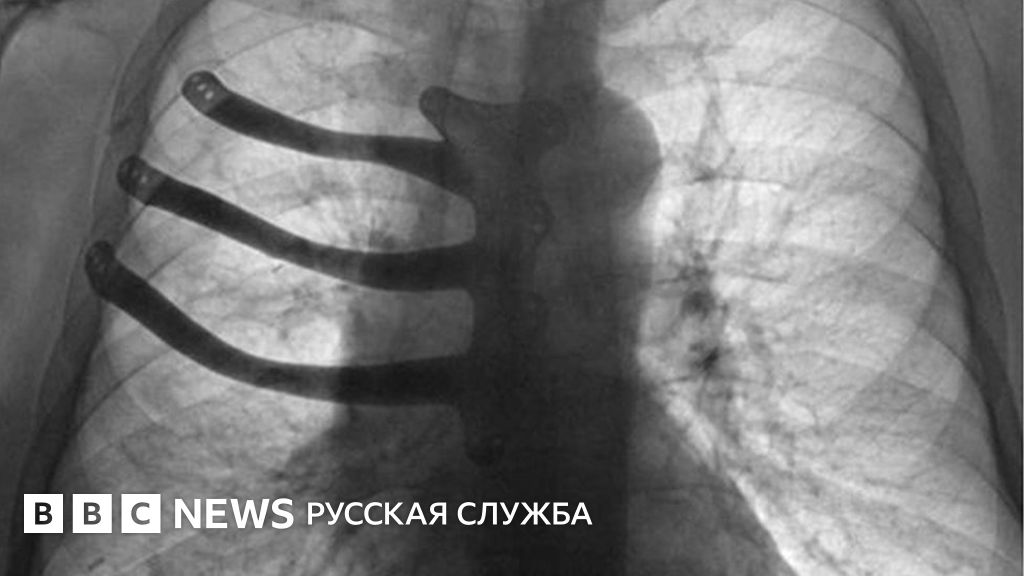

Во время операции по удалению раковой опухоли британские врачи реконструировали больному грудь с помощью 3D-принтера.

71-летнему Питеру Мэггзу удалили три ребра и половину грудинной кости, поместив вместо них протез.

Но благодаря технологии 3D-печати врачи смогли изготовить для больного индивидуальный имплантат из титанового сплава.

Считается, что это один из первых случаев печати подобных протезов в Британии.